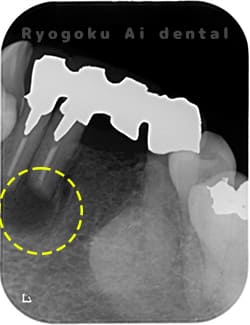

術後1年後レントゲン

-

- 原因

- 歯根嚢胞

- 治療内容

- 歯根端切除法

- 治療費用

- ¥77,000

下の前歯の違和感が取れない、響く感じも強いとのことでご来院された患者様です。歯根端切除術を行い、術後の経過も良好です。

<リスク・副作用>

外科手術のため、術後に出血、痛みや腫れ、違和感を伴います。口腔内の状態によっては適応できないことがあります。歯根端切除で治らなければ抜歯を検討しなくていけない場合もあります。